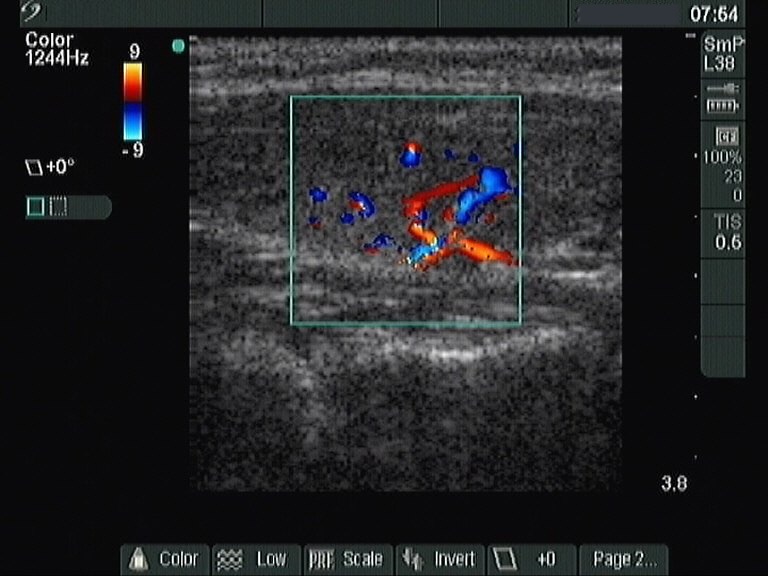

Ultrasonography: the thyroids were moderately hypoechogenic. There was a lesion with similar echo structure in the central part of the left lobe. The nodule displayed a halo sign and both perinodular and intranodular blood flow.